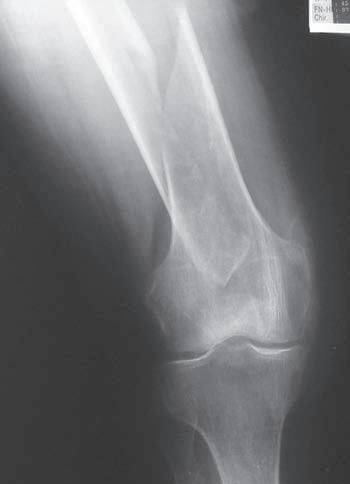

Obr. 2.1 Jednoduchá příčná zlomenina tibie, typ A podle AO klasifikace. Současně je přítomná nedislokovaná nitrokloubní zlomenina proximální části